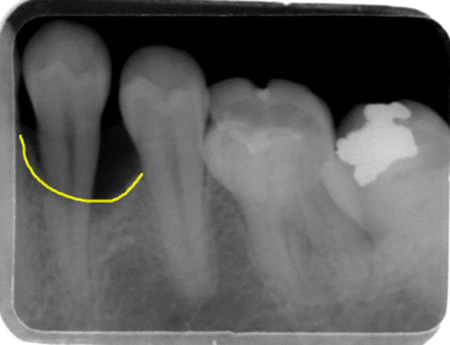

60代の男性の方で歯周病を含めた全般的な検査と治療を希望されて来院しました。自覚症状はないのですが、レントゲン写真上で歯の周りの骨が吸収されているのがわかります。

(写真左)治療には、再生療法を選択し、Gem21 という組織再生誘導薬剤を用いました。1年後のレントゲン写真(写真右)では、骨の欠損部が新生骨によって埋められているのが確認されます。